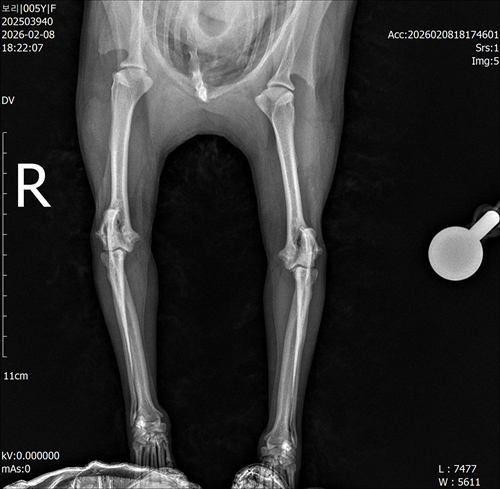

강아지 슬개골탈구 진단 받았습니다 몇군데 병원을 다녀봤는데 진단이 달라 궁금해서 질문 해봅니다 일단 저희 강아지는 오른쪽 다리를 갑자기 들고 다니고 절어 병원을 방문하게 되었고요 왼쪽은 증상이 없지만 오른쪽만 있는 상태였습니다 첫번째랑 두번째 병원에서는 슬개골 탈구 진행중이고 왼쪽이 3기 오른쪽이 2기 정도라고 했습니다 하지만 왼쪽은 아예 빠져있어 증상도 없고 아파하지도 않는다고 했고 오른쪽은 빠졌다 안빠졌다 해서 증상이 있다고 했고 십자인대가 파열된 걸론 보이지 않는다고 했습니다 그래서 양쪽 슬개골탈구 수술만 진행하면 된다고 했고요 근데 세번째 병원에서는 둘다 왼쪽이 좀 더 심한 슬개골 탈구 3기 정도라고 했고 오른쪽만 십자인대 부분파열이 보인다고 했습니다 그래서 십자인대 파열이 아닌 왼쪽은 굳이 수술할 필요가 없고 나중에 십자인대 파열이 오거나 증상이 나타나면 그때 수술하면 된다고 했습니다 그래서 오른쪽 슬개골탈구 수술과 tplo를 하는 방식으로 수술을 한다고 했습니다 여기서 궁금한점은

1. 십자인대 파열이 사진상으론 보이지 않는다고 하는데 사진상으로 알 수 있는 건가요?

4. 사진상으로 십자인대와 슬개골 수술을 같이 해야할까요? 5. tplo 수술방법이 가장 안전하고 좋은 수술방법인가요?